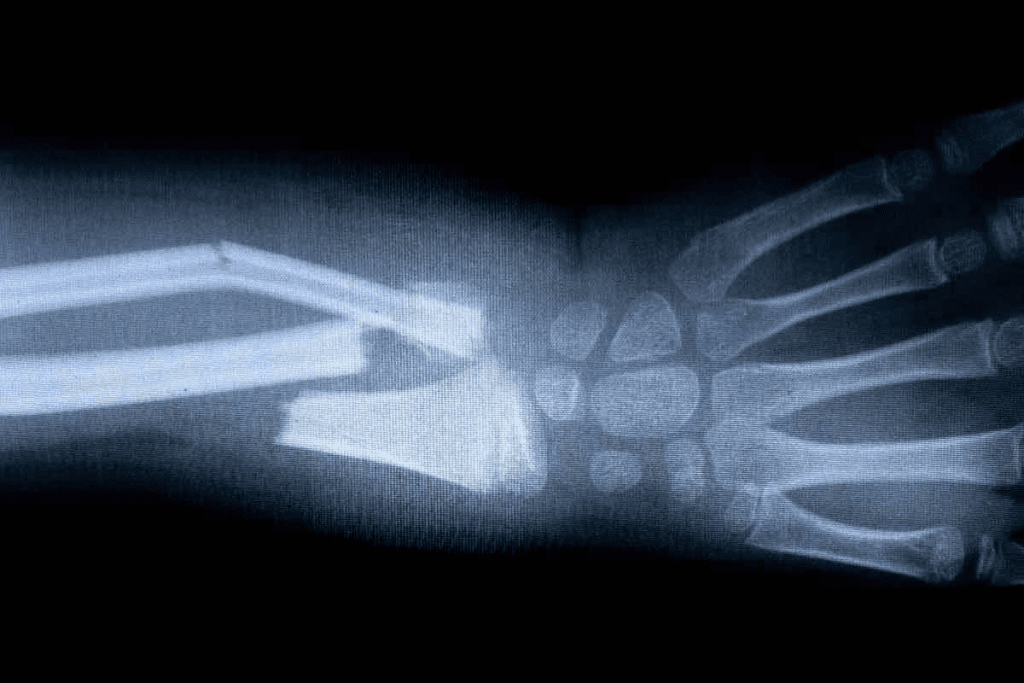

Acute vs. Healing Fractures on Bone Scan

Fractures show up on bone scans because of the bone’s repair work. New fractures have a lot of activity. Healing fractures show less activity as they mend.

It’s important to tell if a fracture is new or healing. Acute fractures need quick treatment and pain relief. Healing fractures need careful watching and maybe rehab to heal right.

Timeline of Uptake Following Bone Trauma

How fast a bone scan shows activity after an injury depends on the injury. Usually, activity goes up in 24-48 hours, peaks in 2-4 weeks, and then goes down as the bone fixes itself.

| Time Frame | Uptake Pattern | Clinical Significance |

| 0-48 hours | Increased uptake | Initial response to injury |

| 2-4 weeks | Peak uptake | Active bone repair |

| 4-6 months | Gradual decrease in uptake | Bone healing and remodeling |

Knowing this timeline helps doctors understand bone scans better. It helps match the scan results with what the patient is feeling and going through.